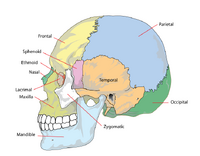

The human skull is generally considered to consist of 22 bones—eight cranial bones and fourteen facial skeleton bones. In the neurocranium these are the occipital bone, two temporal bones, two parietal bones, the sphenoid, ethmoid and frontal bones.

The bones of the facial skeleton (14) are the vomer, two inferior nasal conchae, two nasal bones, two maxilla, the mandible, two palatine bones, two zygomatic bones, and two lacrimal bones. Some sources count a paired bone as one, or the maxilla as having two bones (as its parts); some sources include the hyoid bone or the three ossicles of the middle ear, the malleus, incus, and stapes, but the overall general consensus of the number of bones in the human skull is the stated twenty-two.

Some of these bones—the occipital, parietal, frontal, in the neurocranium, and the nasal, lacrimal, and vomer, in the facial skeleton are flat bones.

The many processes of the skull include the mastoid process and the zygomatic processes.